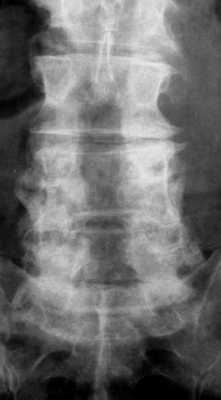

МРТ поясничного отдела позвоночника. Т2-взвешенная сагиттальная МРТ. Стеноз позвоночного канала.